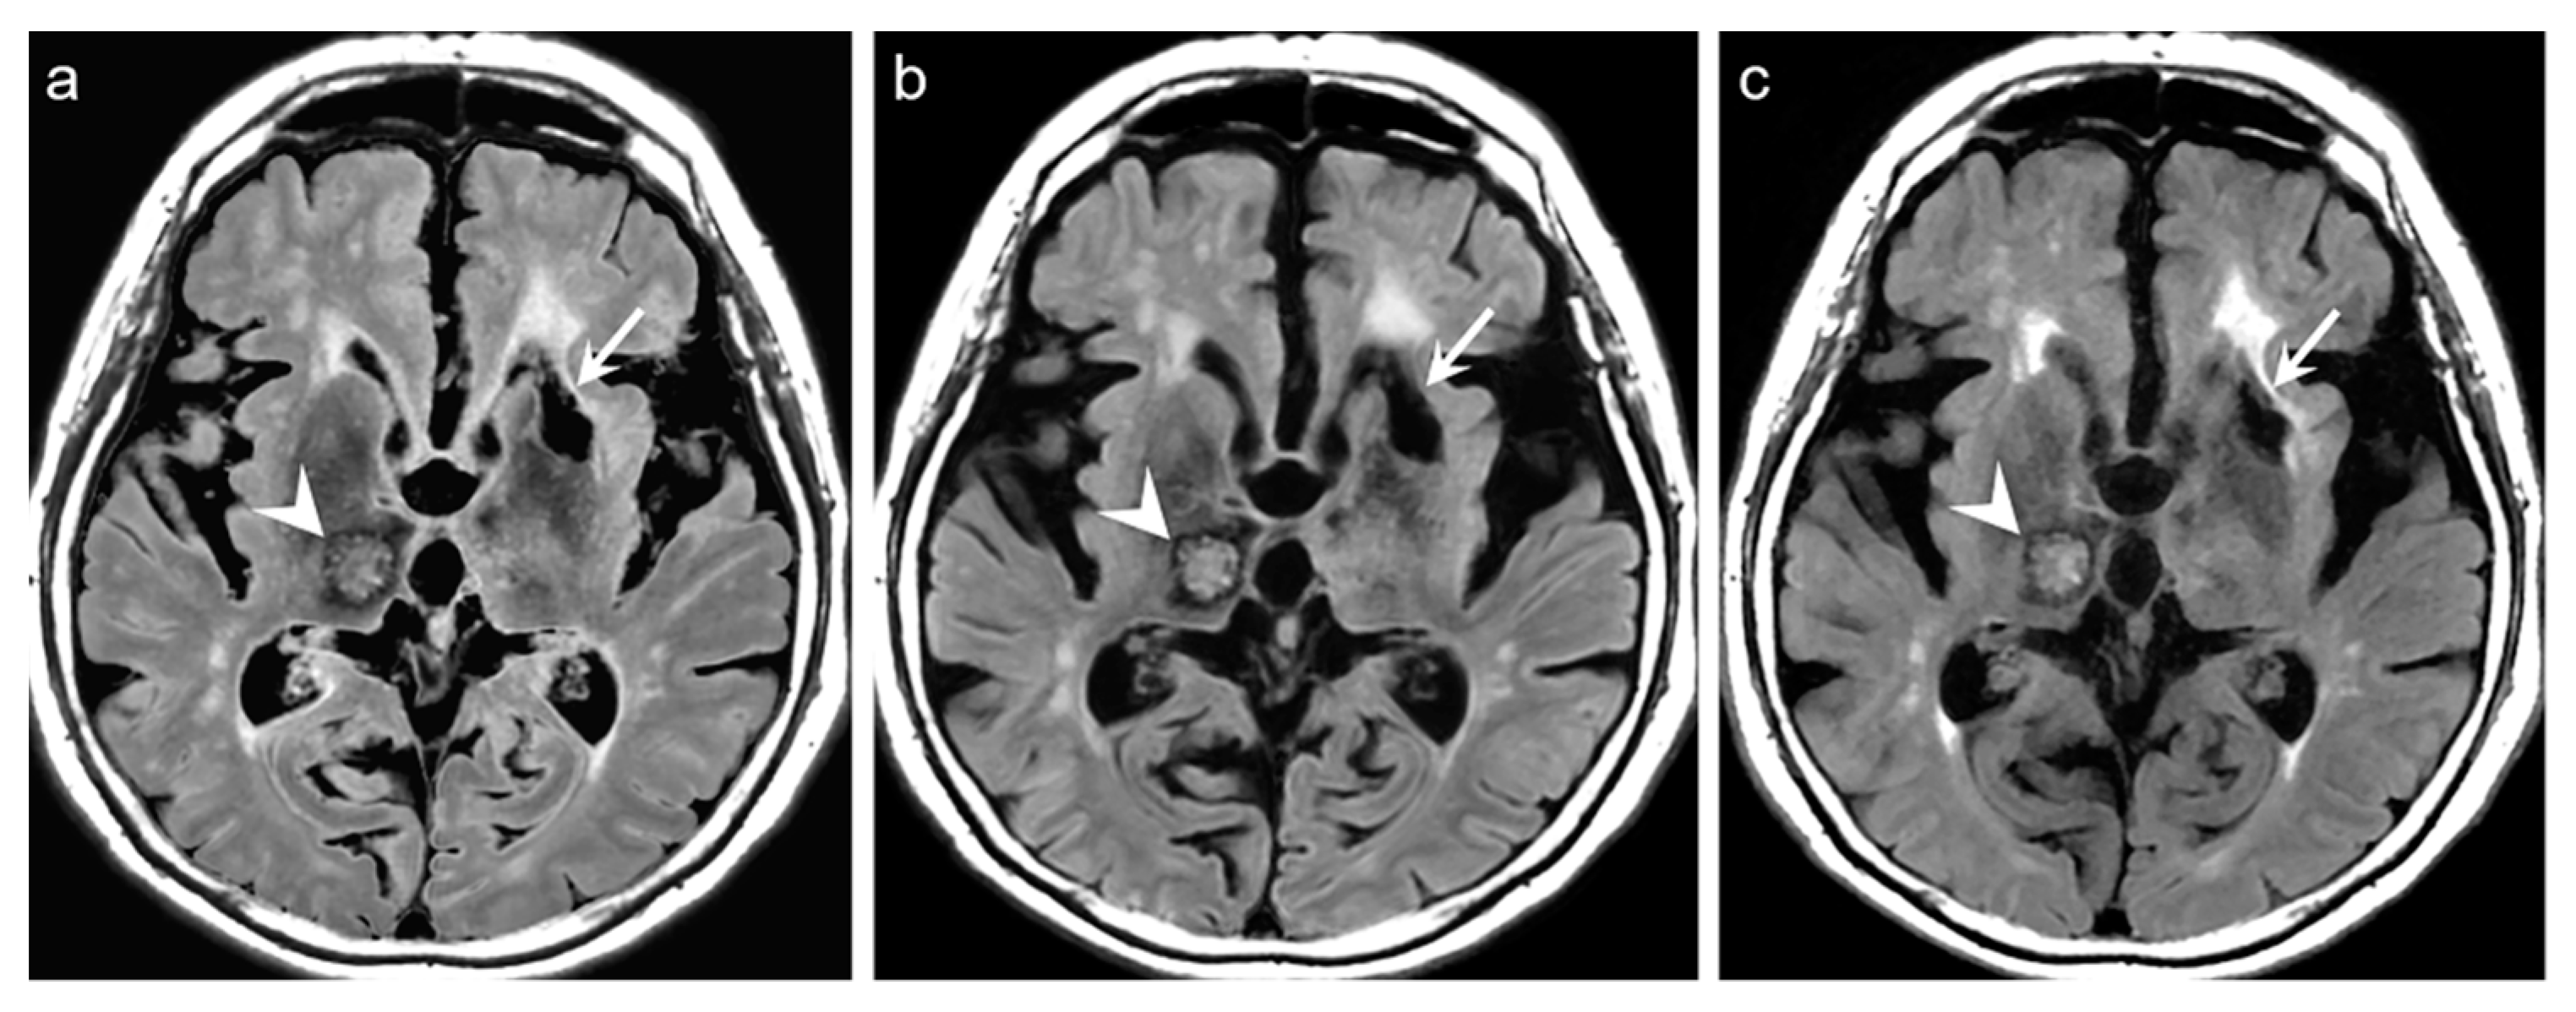

Representative examples are depicted in

Figure 2,

Figure 3,

Figure 4 and

Figure 5.